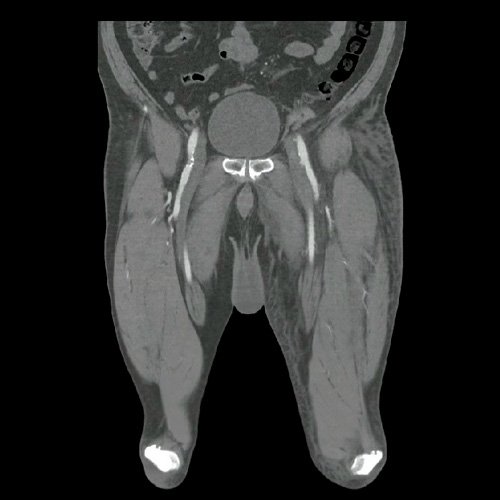

• TAC de abdomen y pelvis con contraste EV (Día 10): El hígado es de forma, tamaño y situación habituales. Su superficie es lisa, y sus bordes son agudos. No presenta alteraciones densitométricas ni efectos de masa focales. La vía biliar intra y extrahepática es de calibre conservado. La vesícula biliar es de forma, tamaño y situación normales, sin imágenes que sugieran la presencia de litiasis. Tener en cuenta que este método puede pasar por alto litiasis colesterínicas. El bazo es de forma, tamaño y situación normales. El eje esplenoportal es de calibre y trayecto conservado. El páncreas es de características normales. El conducto de Wirsung es de calibre conservado. Las glándulas adrenales son normales. Ambos riñones son de forma, tamaño y situación habituales. Sin evidencia de alteraciones calicopiélicas ni ureterales. Quistes simples corticales en riñón izquierdo, el mayor de ellos en polo superior, que mide 16 mm. Discreta reticulación de la grasa perirrenal bilateral. La aorta, las arterias ilíacas primitivas, internas, externas y femorales, son de calibre y trayecto conservado. La vena cava inferior y las venas ilíacas primitivas, internas, externas y femorales son de calibre y trayecto conservados. Filtro de vena cava inferior infrayacente a venas renales. No se observan adenomegalias intraperitoneales, retroperitoneales, ilíacas ni inguinales. No se observan alteraciones a nivel del tracto gastrointestinal. Abundante contenido de materia fecal en el colon. Vejiga con escasa repleción. La próstata y las vesículas seminales son de características normales. No se observa líquido libre ni neumoperitoneo Presenta aumento del diámetro de la raíz del muslo izquierdo con respecto a su contralateral, asociado a edema de los tejidos blandos superficiales. Reticulación de los tejidos blandos de la región inguinal izquierda, de mayor jerarquía que en estudio anterior, con tendencia a coleccionar. Además se observan ganglios locorregionales aumentados en número y tamaño sin alcanzar rango megálico. Se observa inmediatamente infrayacente a los antes mencionado, un área hiperdensa que realza en fase venosa, con centro hipodenso, que mide 2.2 cm x 1.4 cm, ya visualizado en tomografía previa, sin cambios. Calcificaciones en conducto inguinal bilateral. Hidrocele bilateral. Marcados cambios artrodegenerativos de la columna lumbosacra y coxo-femorales.

TAC de tórax, abdomen y pelvis con contraste EV (Día 10) Corte axial